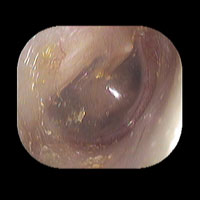

右急性中耳炎(中等症)

鼓膜がやや赤くなっています。鼓膜の奥に膿が透けて見えています。鼓膜の腫れはありません。抗生剤の内服で鼓膜切開を行わずに16日目で治りました。

16日目